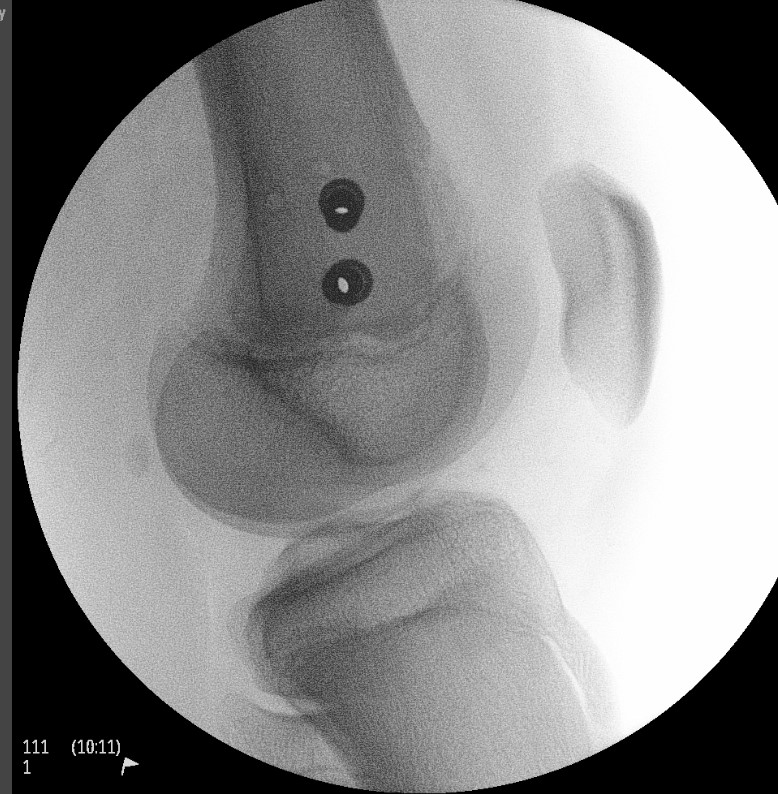

Xray

Salter Harris I

Salter Harris II